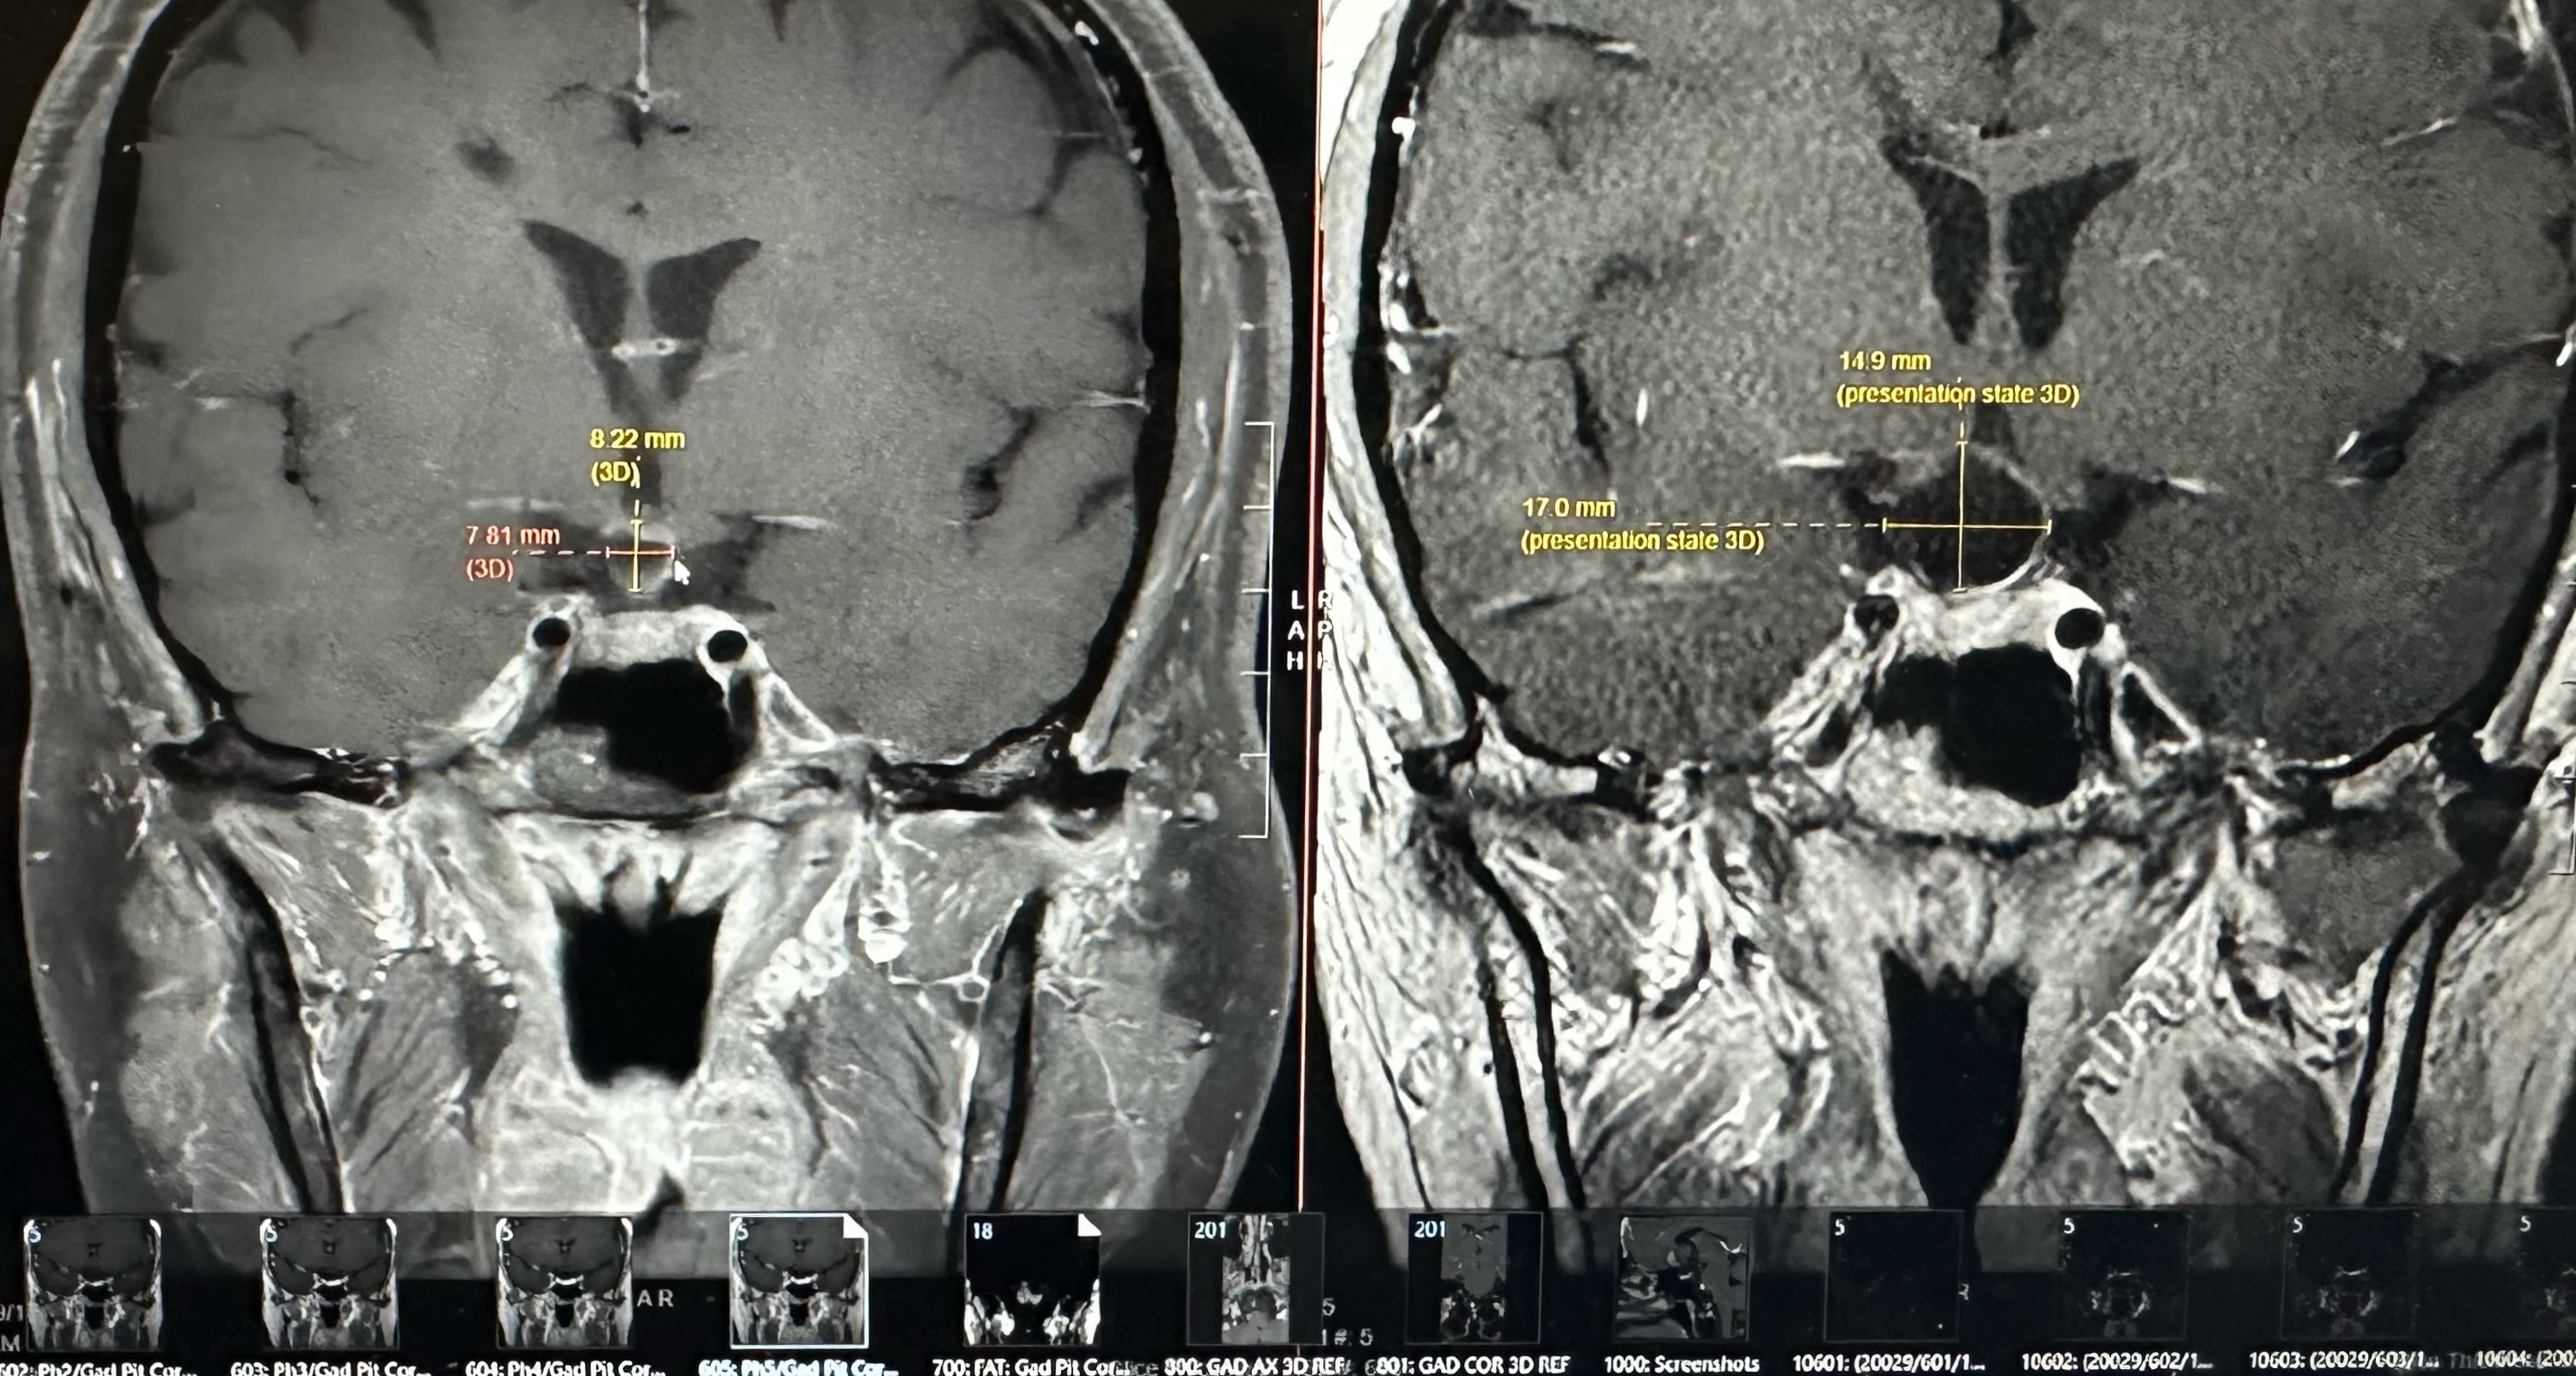

So now I get brain MRIs every 6 weeks, which is intense — but the tumor has a history of growing really fast, so it also keeps me safe. The biggest concern is that if it grows, more damage could be done to my pituitary stalk, optic chiasm, and hypothalamus (these are very important parts of the brain, if you didn't know — they refer to this area as the prime real estate of the brain). I am a very rare unicorn in that my Hypothalamic-Pituitary Axis has no deficiencies after two brain surgeries and two recurrences — even after the first tumor, at 4cm, put extreme strain on it. I am actually being screened again by my new endocrinologist because it's literally unheard of. Looking back, I can see that God definitely had a hand in this miracle. The original misdiagnosis was actually a blessing, because the brain surgeries I had did not harm the most critical part of my brain. My connection with a higher power has definitely brought me through the darkest of times and made my faith stronger. That's the strange and unexpected thing about serious, life-threatening disease — you are forced to go on a spiritual journey, and the way you live, see things, and feel things will forever be different. I'll be honest: I am still in shock that after three years of fighting, I am here and I am okay. Doctors and people look at me and cannot believe I seem and look normal after reading my medical chart. That is my miracle — it still brings me to tears with gratitude. I am not fearful of going through more hardship; I am only annoyed at the thought of having to go back into the process of it — the restriction, the endless blood draws, the weeks filled with appointments, feeling sick, picked, probed, and prodded. Feeling like more of a lab rat than a person, and feeling like my body isn't mine anymore. But I am taking my body back these past couple of weeks and slowly getting physically stronger. Slowly learning to love myself and my body again. I am mentally stronger now than ever, and I know I will always be okay regardless of what comes my way.